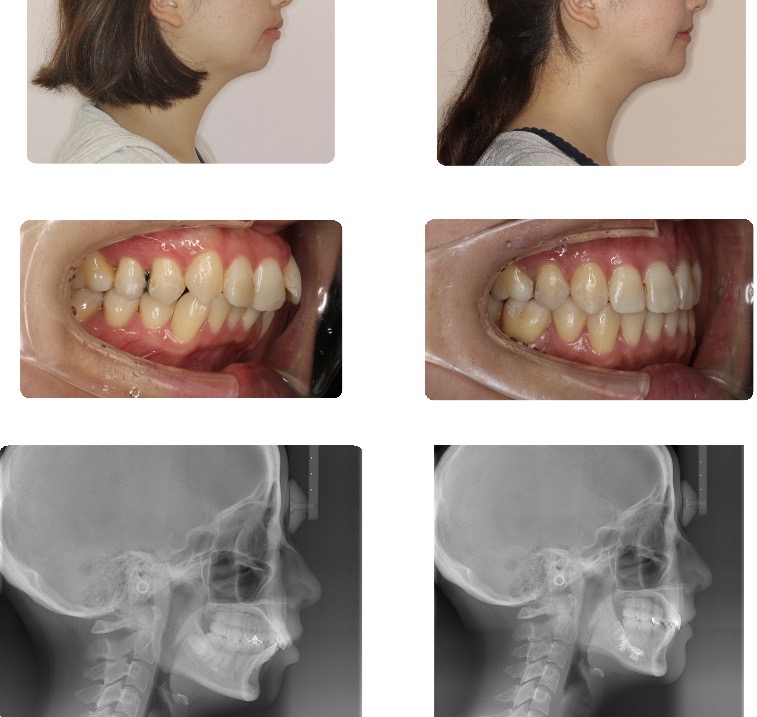

開咬

前歯の後退により開咬を改善でき、同時に口元の突出感が解消されました。前歯で咬みきれるようになり、咀嚼効率が大きく改善しました。

またリラックスした状態での口唇閉鎖が可能となり、プロファイルの良好な改善がなされました。